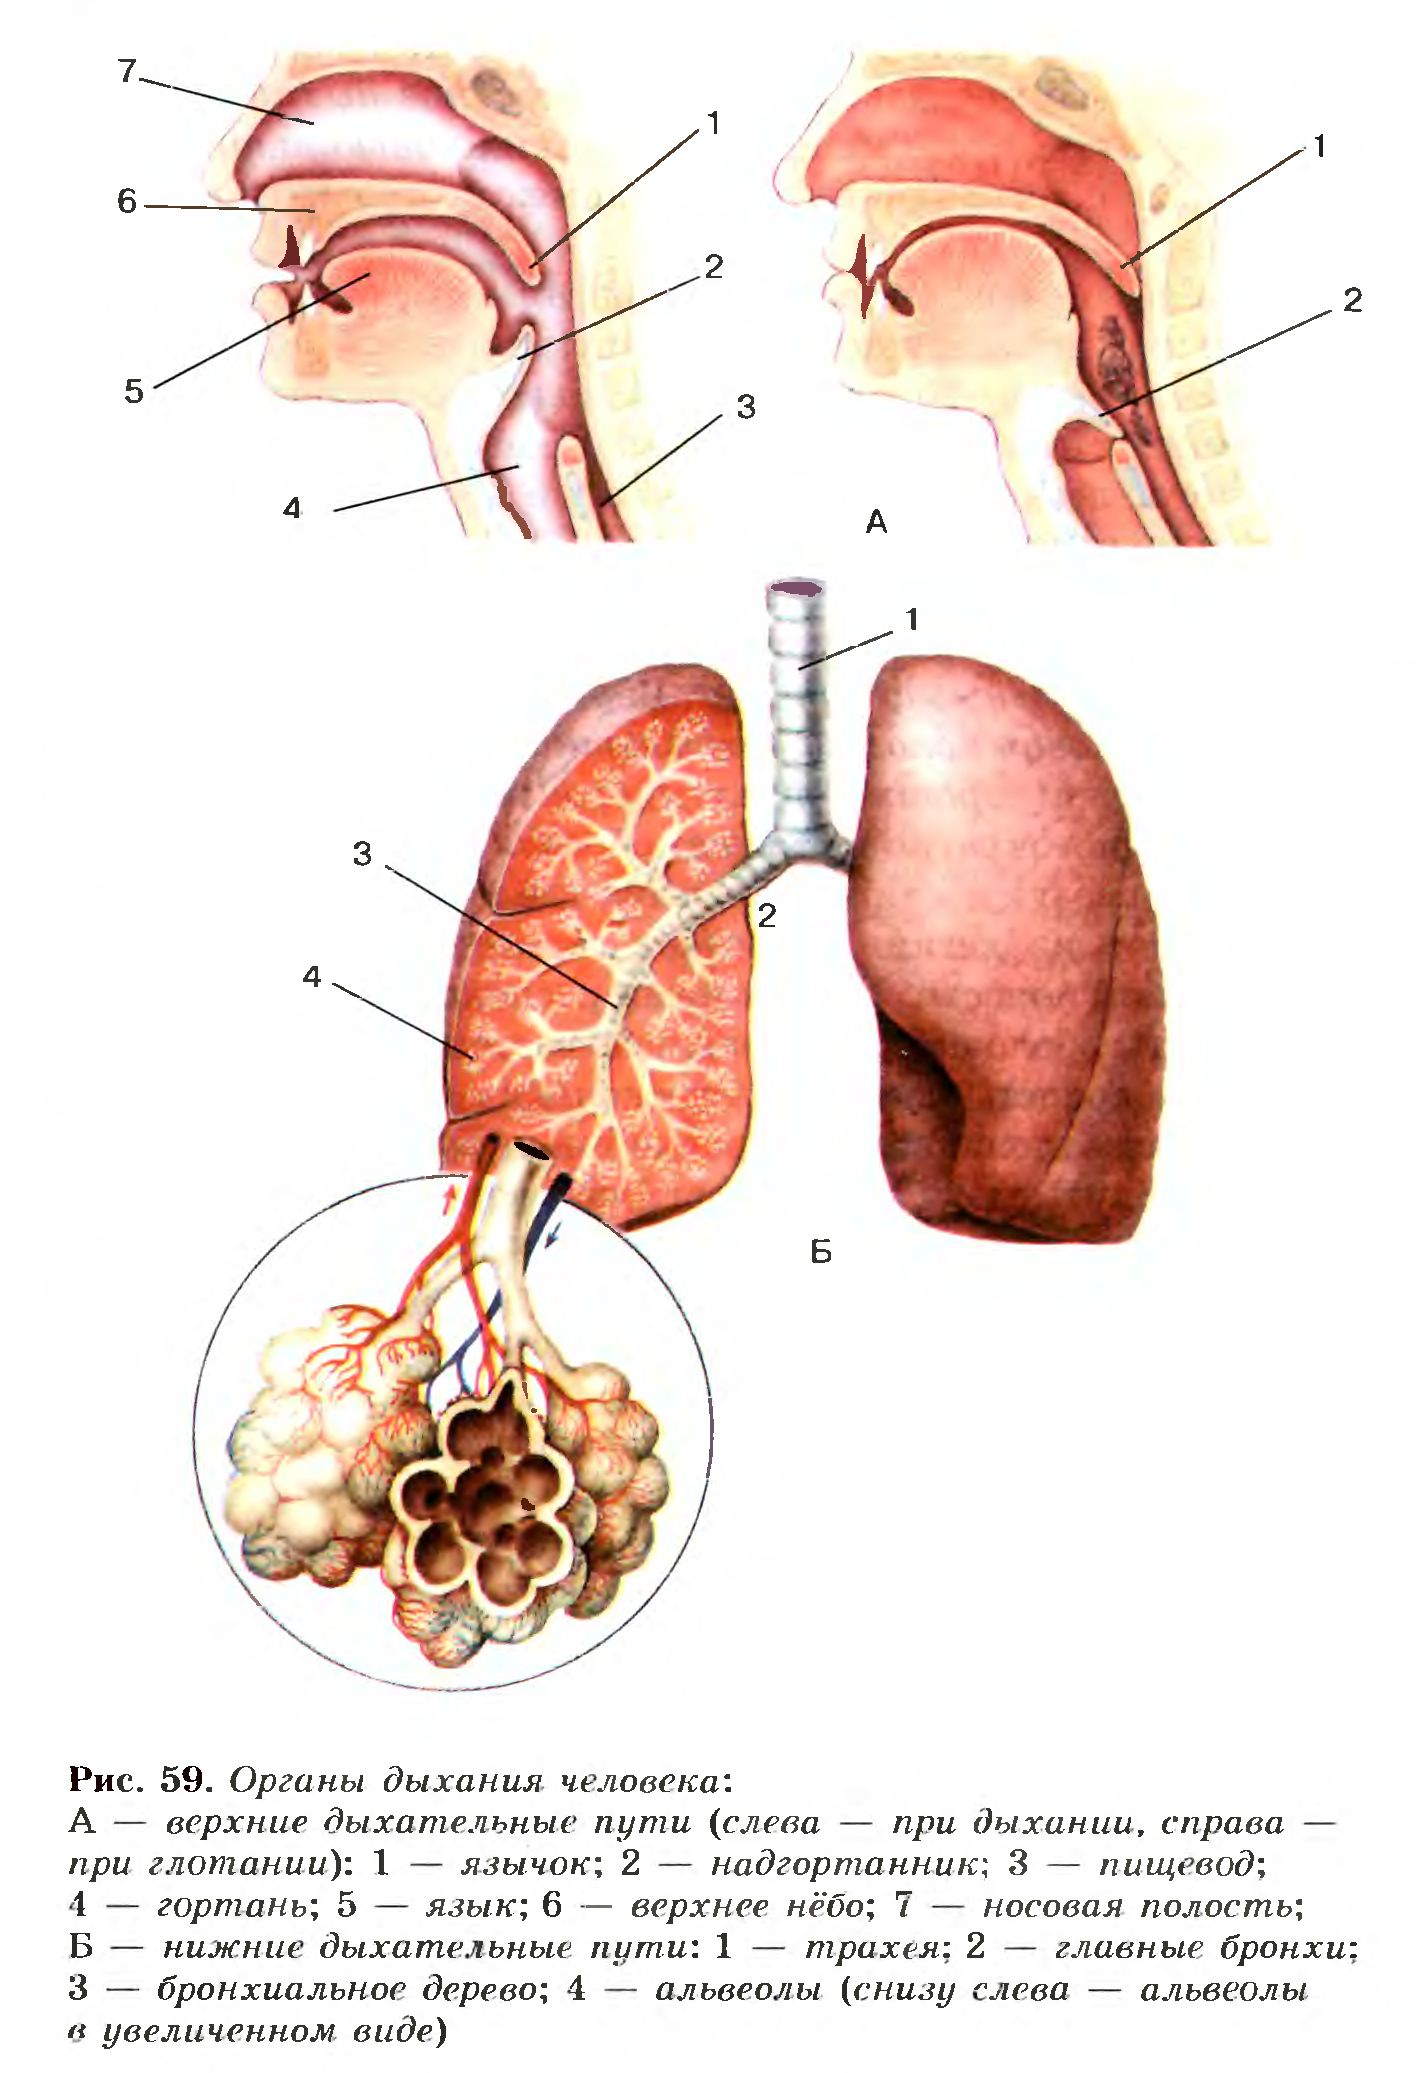

Схема дыхательной системы человека: а — общий план строения; б — строение альвеол; 1 — носовая полость; 2 — надгортанник; 3 — глотка; 4 — гортань; 5 — трахея; б — …

Дыхательные пути представляют собой систему трубок, просвет которых формируется благодаря наличию в них костей и хрящей . Внутренняя поверхность дыхательных путей …

Дыхательнаясистемачеловекасостоитизтканейиорганов,обеспечивающихлегочную вентиляциюилегочноедыхание .К воздухоносным путям относятся: нос, полость носа, носоглотка, …

Дыхательная система (дыхательный аппарат), systema resperatorium, состоит из дыхательных путей и парных дыхательных органов - легких . Дыхательные пути …

Дыхательная система . Дыхание как совокупность процессов, обеспечивающих поступление в организм кислорода и удаление углекислого газа . Органы, входящие в состав верхних …